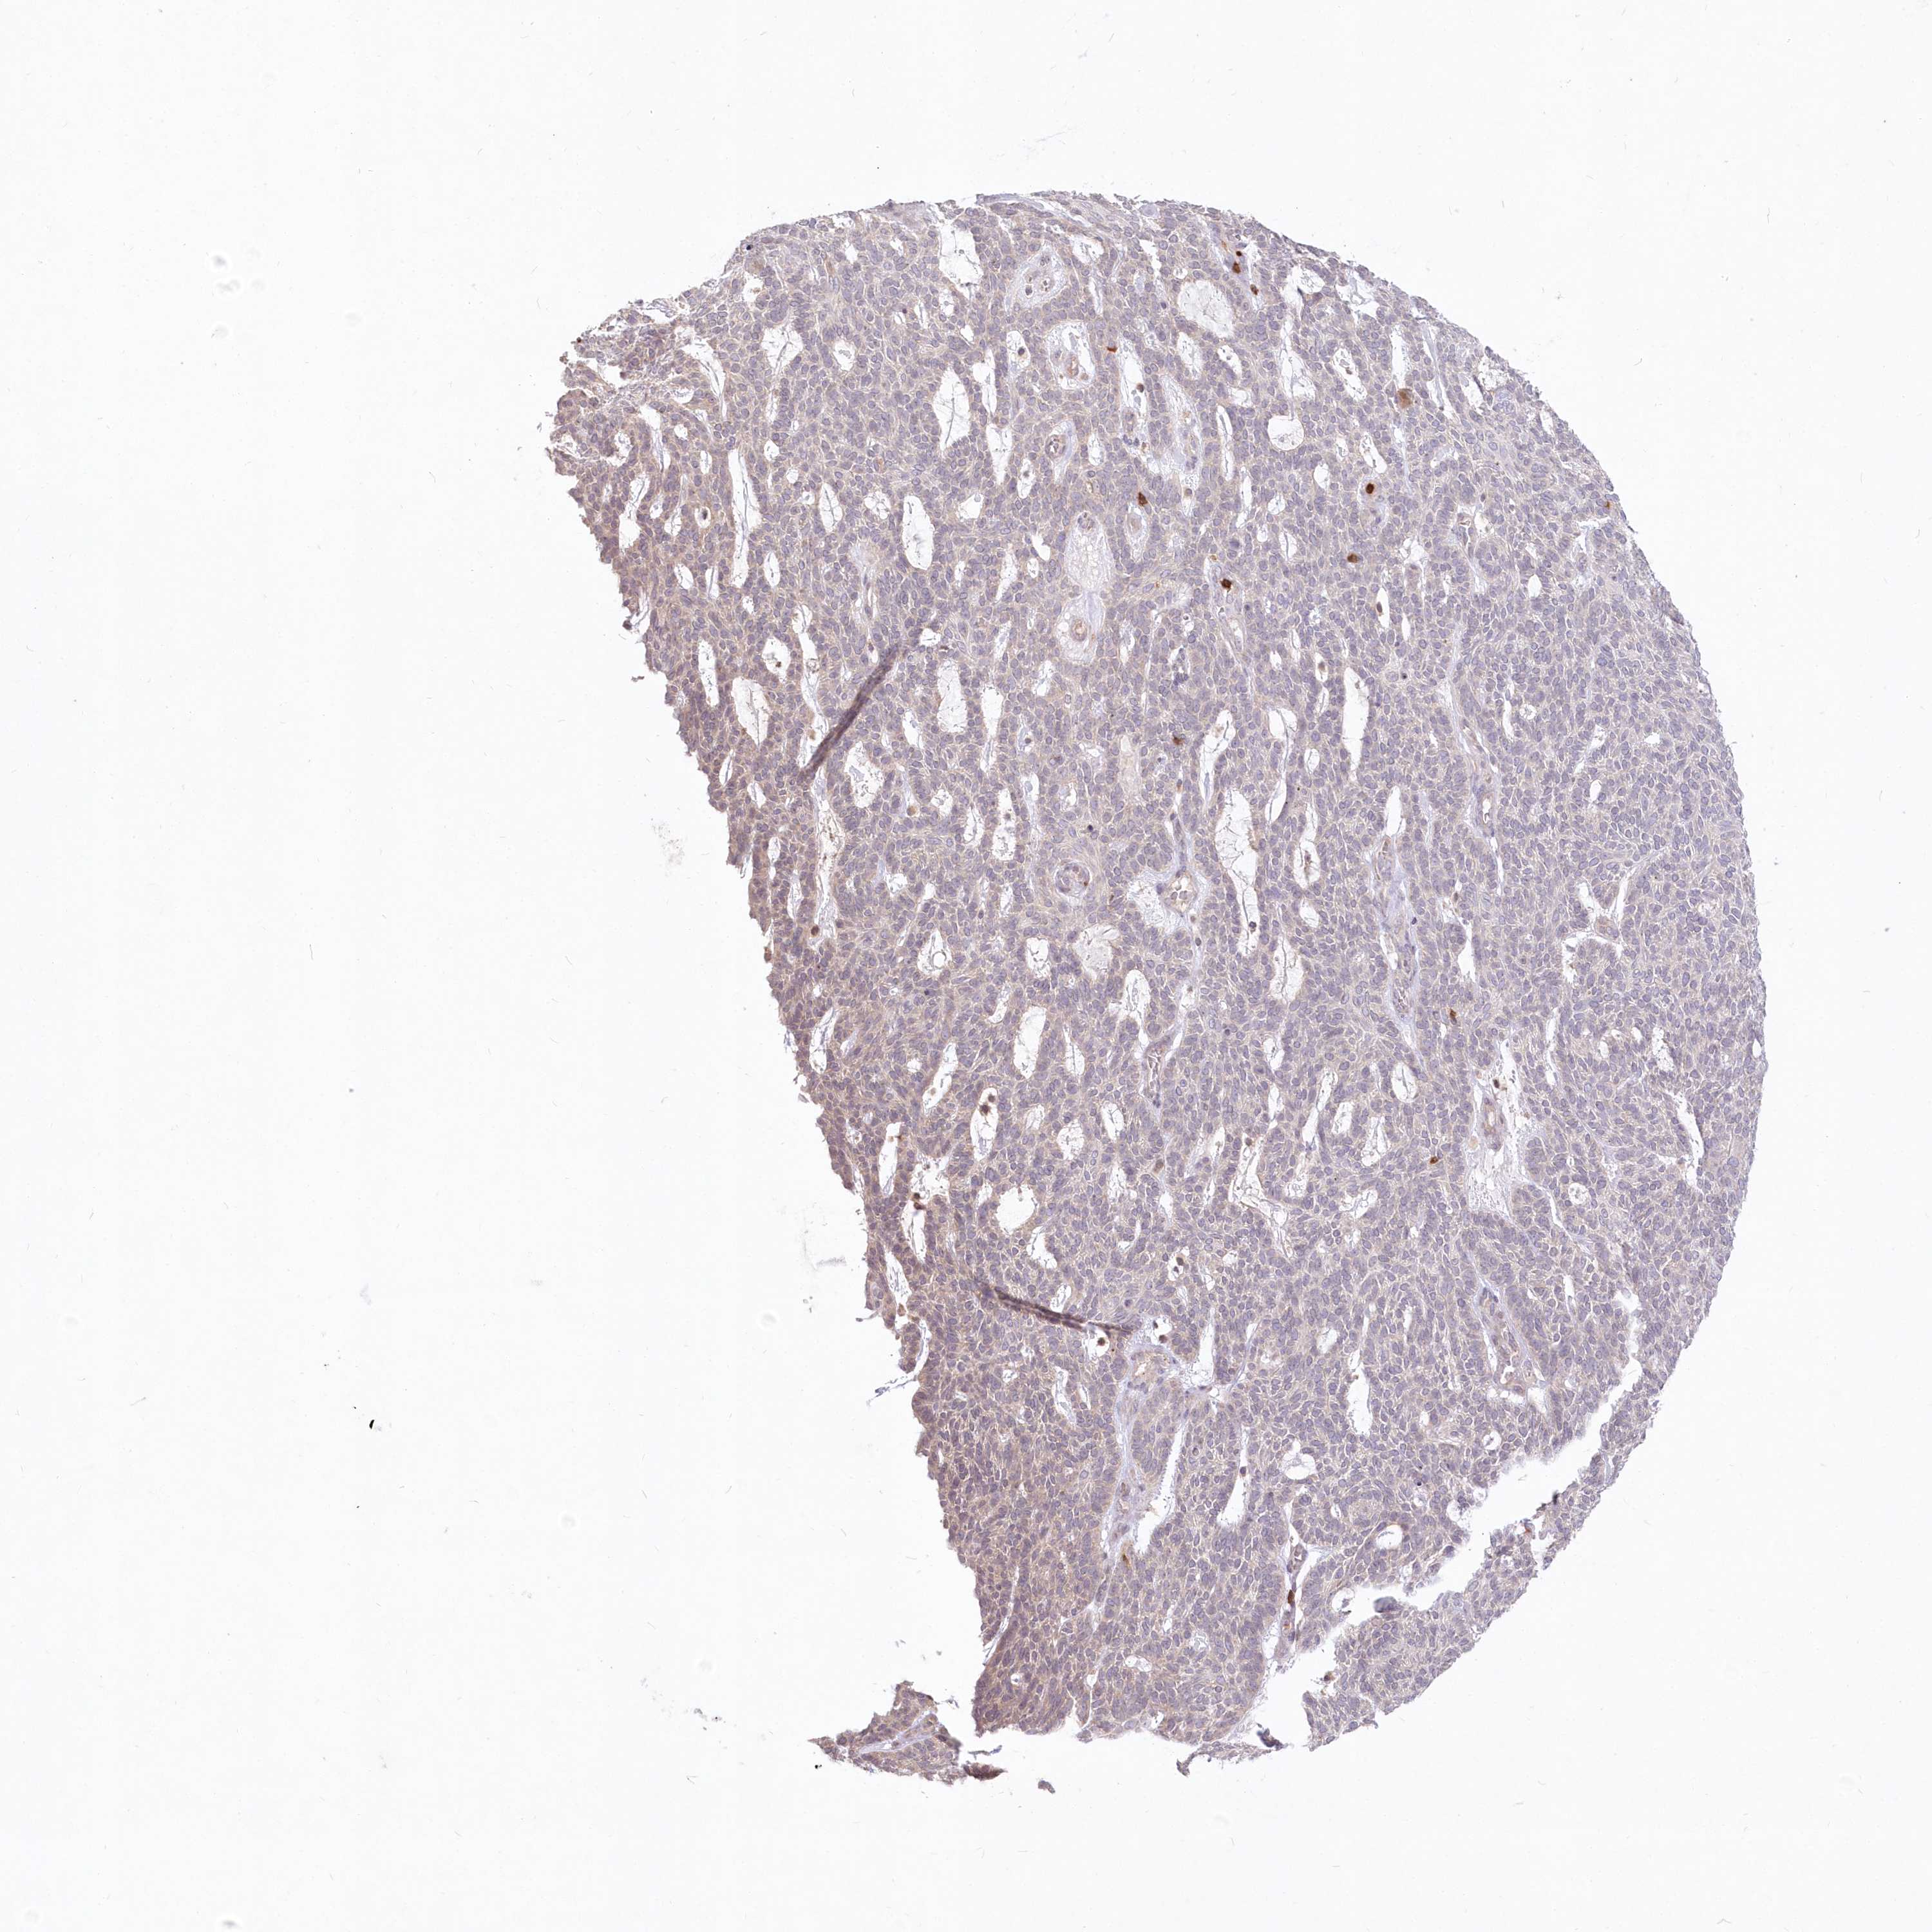

Antibody HPA034515

Basal cell carcinoma